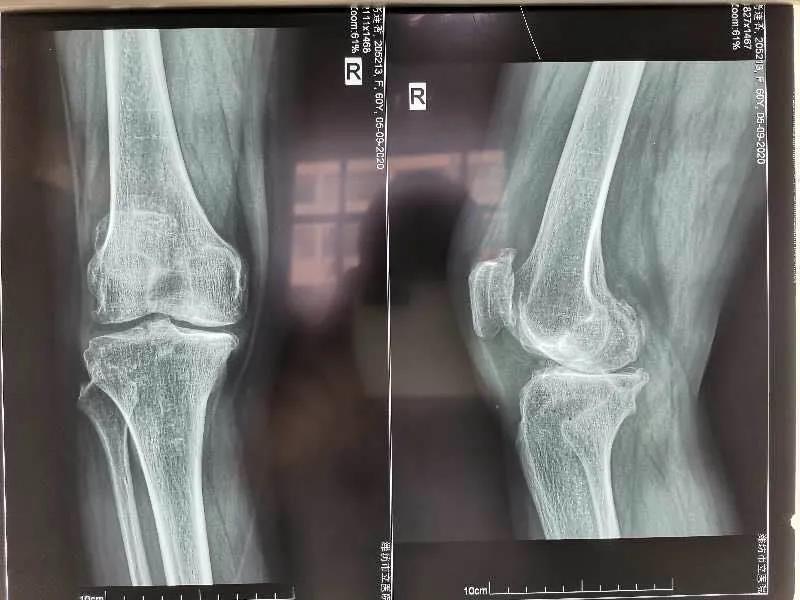

手術(shù)前